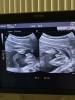

Девочки , уже 20 недель а я до сих пор не знаю точно кто у меня , предположили , что девочка , но не подтвердили на 2 УЗИ надеемся что будет мальчик . У кого так же ?

На первом ничего, на втором как то не уверенно, сказал что похоже как на девочку. Я записалась в платную и на 26 неделе мне сказали, точно, девочка

На первом УЗИ не сказали кто будет, а на втором сказали девочка, посмотрим что скажут на третьем, а так хотели мальчика🥰

Точный пол я узнала на втором скрининге в 21 неделю, а на первом скрининге предположили тоже девочку, но ко второму скринингу моя "девочка" писюн отрастила 😁